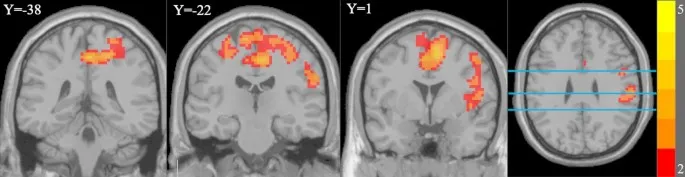

Рис. 4. Области мозга с повышенной FC MFG в группе IGD. Синие горизонтальные линии представляют Y = -38, Y = -22 и Y = 1

Результаты FC MFG

При использовании правой MFG в качестве ROI для анализа FC было обнаружено, что по сравнению с группой HC, FC правой MFG была значительно увеличена с двусторонней SMA, двусторонней прецентральной извилиной, правой постцентральной извилиной, двусторонними медиальными и парацентральными поясными извилинами, двусторонними парацентральными долями, правой надкраевой извилиной, правой дорсолатеральной верхней лобной извилиной, правым роландовым валиком и правой островковой долей в группе IGD (Рис. 4).